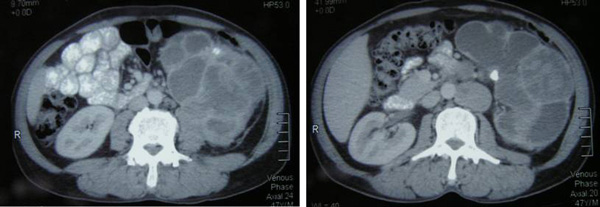

About one and a half months ago, RZ was told by the doctor in Aceh, Indonesia that he had kidney problem. In early March 2012, he came to a private hospital in Penang for further management. A CT scan was done and showed a 10 x 9 cm enhancing lesion in the left kidney with renal vein thrombosis. The right kidney was normal. There were multiple nodules noted in the left upper paraaortic area.  Histopathology report confirmed a poorly differentiated renal cell carcinoma, sarcomatous type, Stage 3 – 4 (T2N2Mx). Four of 8 paraaortic lymph nodes had metastatic disease.